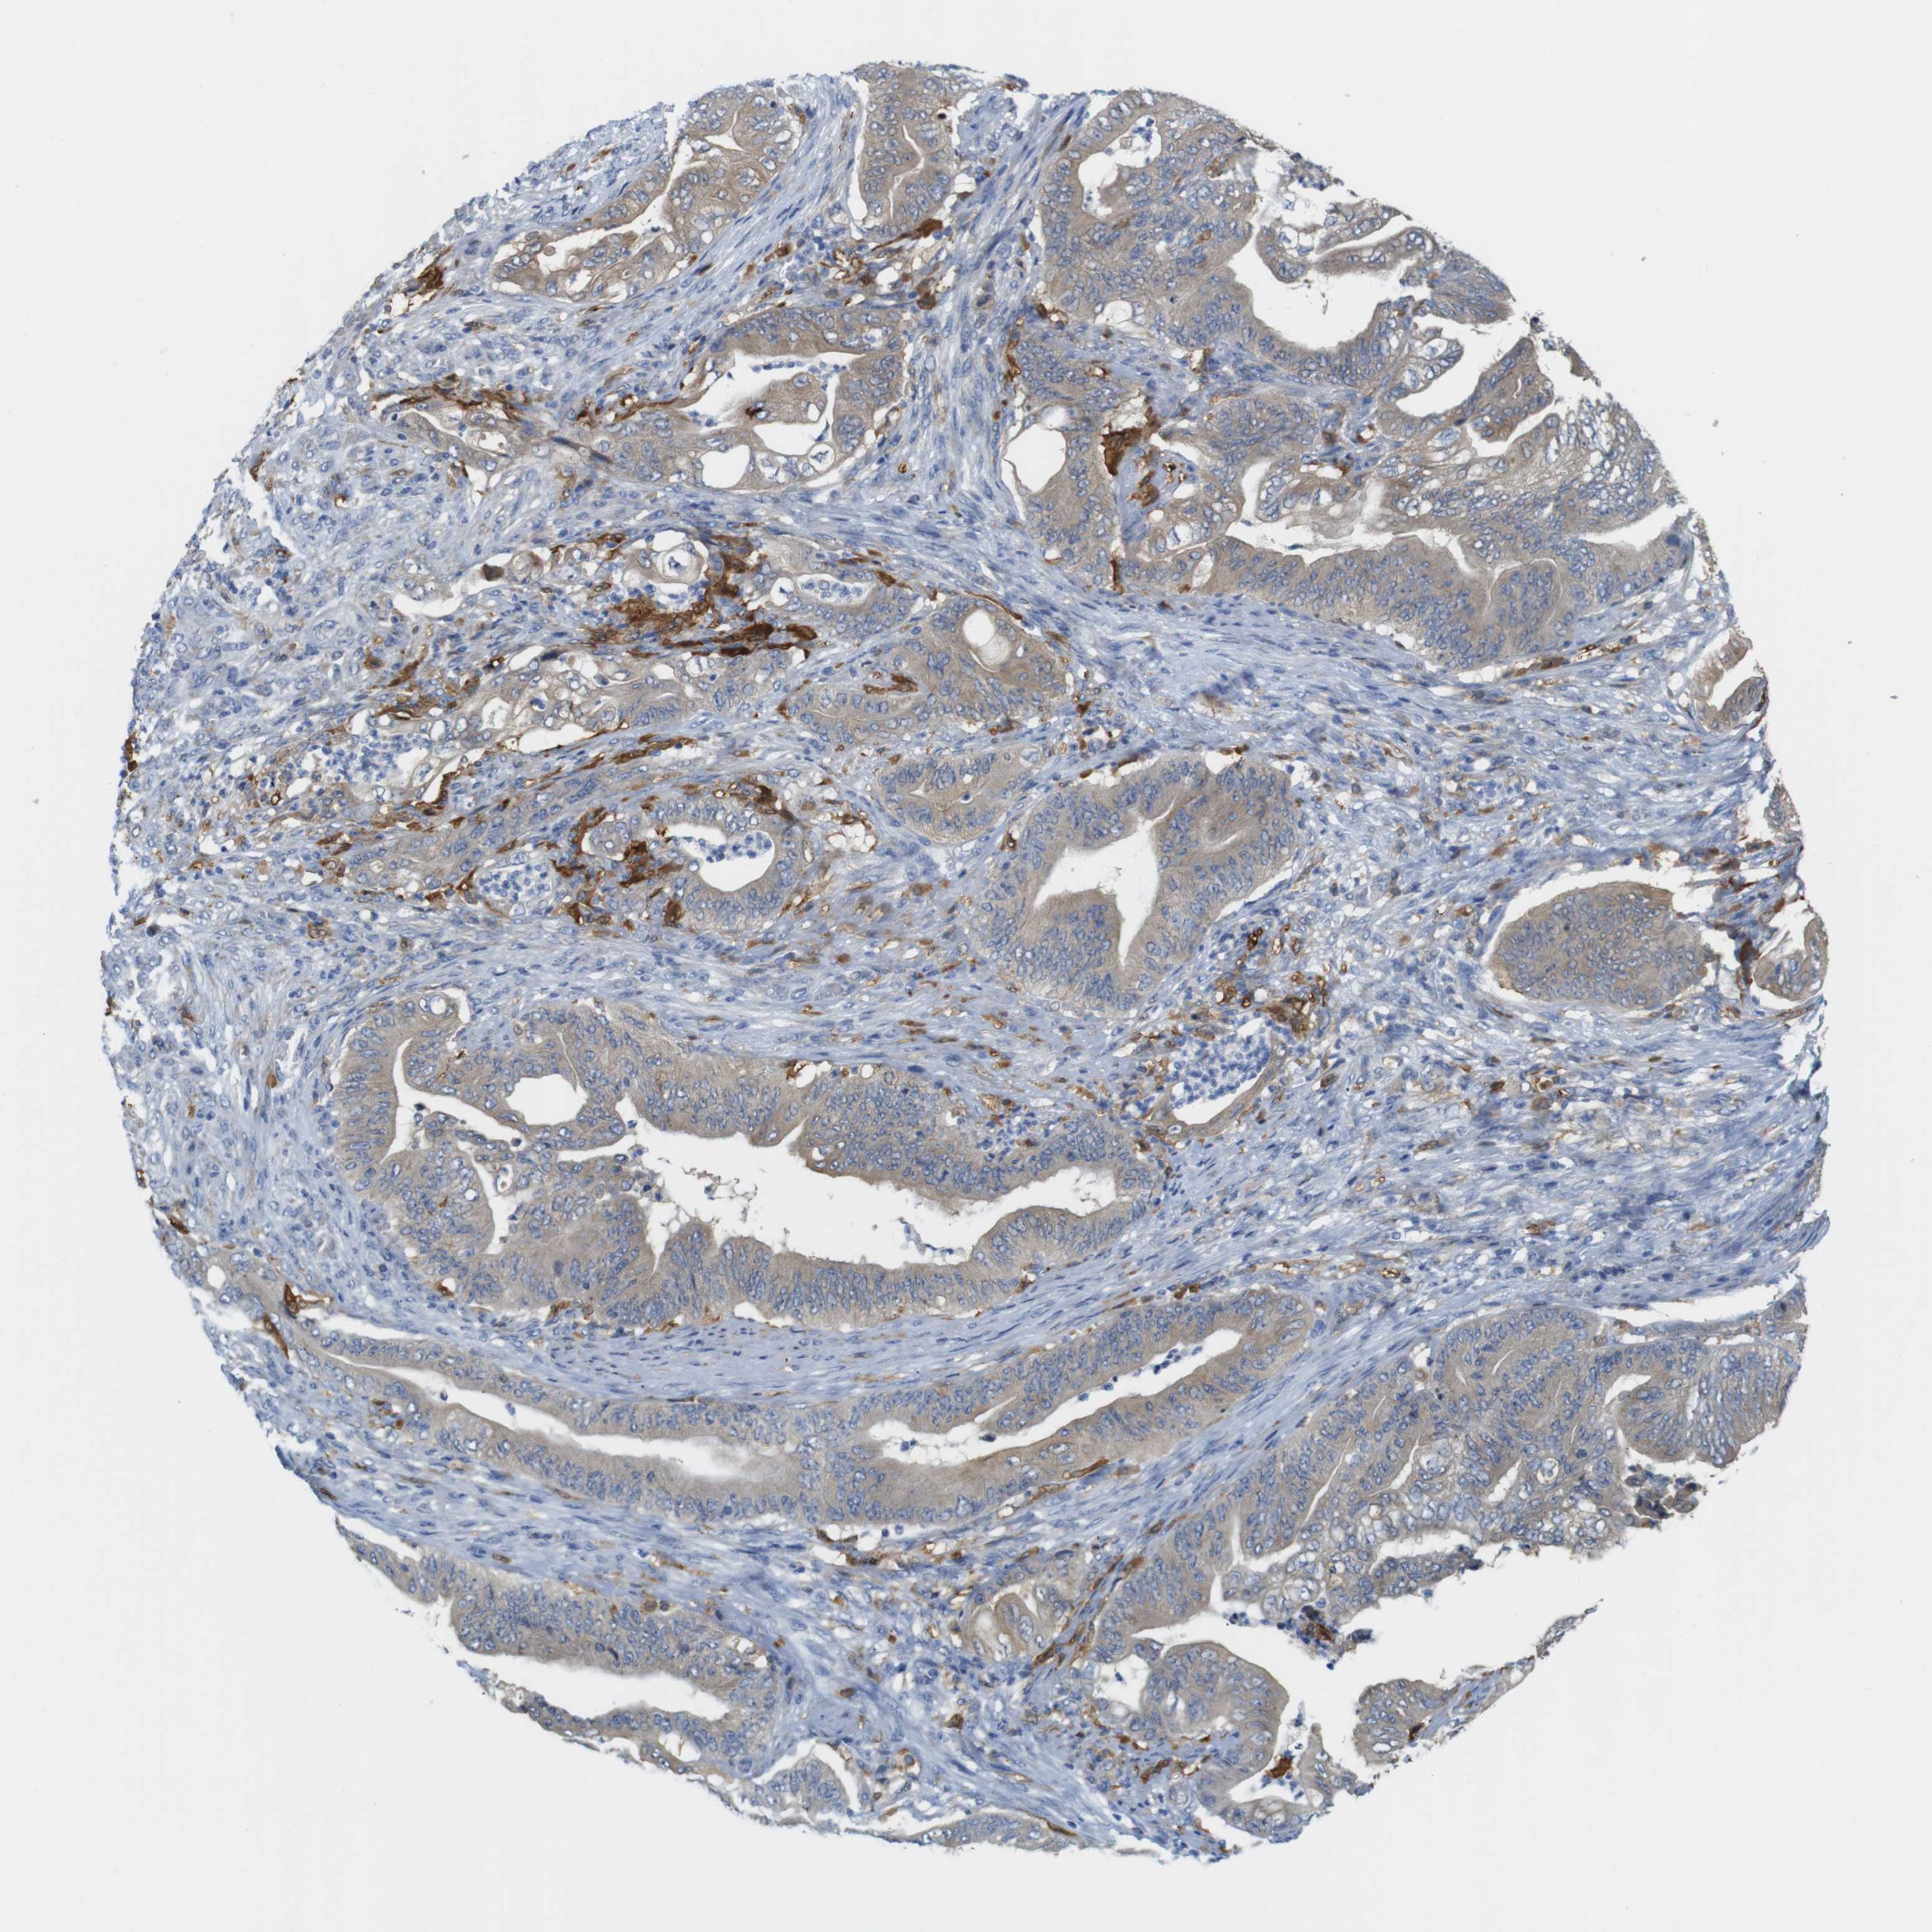

STOMACH CANCER - Protein expressioni

A mouse-over function shows sample information and annotation data. Click on an image to view it in a full screen mode. Samples can be filtered based on level of antibody staining by selecting one or several of the following categories: high, medium, low and not detected. The assay and annotation is described here.

Note that samples used for immunohistochemistry by the Human Protein Atlas do not correspond to samples in the TCGA dataset.

Antibody stainingi

Antibody staining in the annotated cell types in the current human tissue is reported as not detected, low, medium, or high, based on conventional immunohistochemistry profiling in selected tissues. This score is based on the combination of the staining intensity and fraction of stained cells.

Each image is clickable and will lead to virtual microscopy that enables deeper exploration of all samples and also displays staining intensity scores, fraction scores and subcellular localization as well as patient and tissue information for each sample.

Antibody HPA013994

Antibody HPA013995

Staining

High

Medium

Low

Not detected

Intensity

Strong

Moderate

Weak

Negative

Quantity

>75%

75%-25%

<25%

None

Location

Nuclear

Cytoplasmic/membranous

Cytoplasmic/membranous,nuclear

Adenocarcinoma, NOS

Adenocarcinoma, High grade